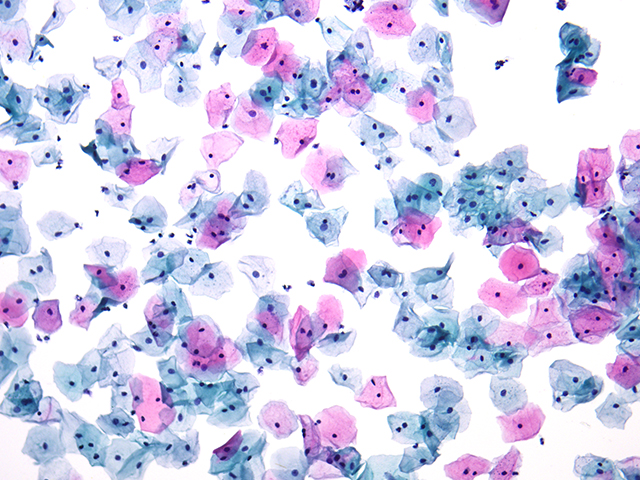

近期,有客户针对组织切片拍照观察提出了特定需求。其主要应用集中在病理和毒理生物组织切片的观察拍照,因而急需一台带成像功能的生物显微镜。这要求显微镜能够清晰地呈现组织切片的微观结构,准确捕捉每一个关键细节,以便为后续的分析诊断提供可靠依据。

明美提出了生物显微镜ML31 搭配高像素摄像头解决方案。生物显微镜ML31 具备良好的光学性能,能够提供清晰、稳定的成像基础。而与之搭配的大靶面高像素相机更是如虎添翼,在明场拍照时可以呈现出清晰的图像效果。